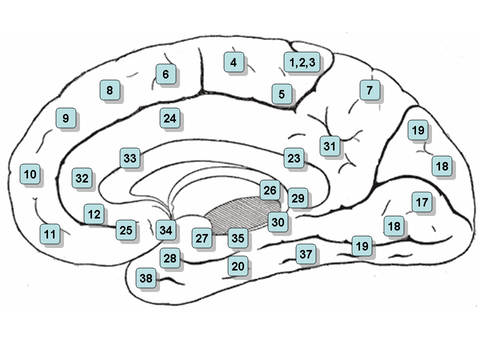

Medial surface of the brain with Brodmann's areas numbered. | |

Ectorhinal area 36 is a subdivision of the cytoarchitecturally defined temporal region of cerebral cortex. With its medial boundary corresponding approximately to the rhinal sulcus it is located primarily in the fusiform gyrus. Cytoarchitecturally it is bounded laterally and caudally by the inferior temporal area 20, medially by the perirhinal area 35 and rostrally by the temporopolar area 38 (H) (Brodmann-1909).

Together with Brodmann area 35, it comprises the perirhinal cortex.